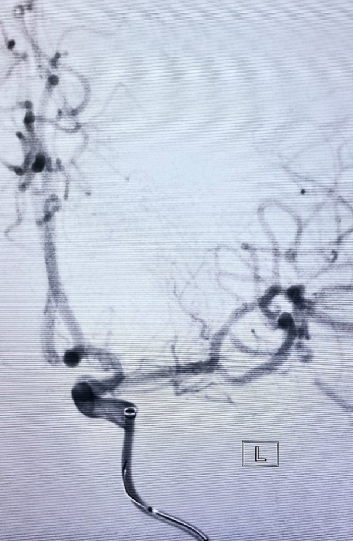

入院影像检查

导丝怎么扩【载药时代 球扩天下】NOVA DES®颅内药物洗脱支架在大脑中动脉重度狭窄中的应用两例!_https://www.jmylbn.com_新闻资讯_第5张

导丝怎么扩【载药时代 球扩天下】NOVA DES®颅内药物洗脱支架在大脑中动脉重度狭窄中的应用两例!_https://www.jmylbn.com_新闻资讯_第6张

重要影像结论DSA:左侧颈内动脉起始处重度狭窄、左侧大脑中动脉M1段偏心斑块伴重度狭窄。